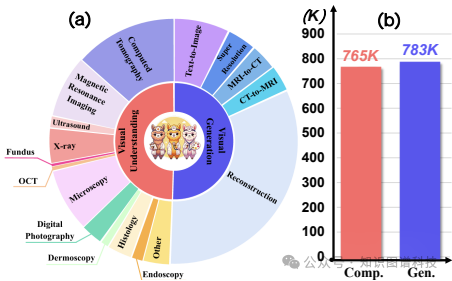

数据集:研究团队构建了VL-Health数据集,包括七个理解任务和五个生成任务。数据集涵盖了多种医疗图像模态和疾病类型,以确保模型的泛化能力。

全面的训练数据集

:设计了VL-Health数据集,包含七种理解任务和五种生成任务,为统一医疗多模态模型的训练提供了丰富的数据支持。